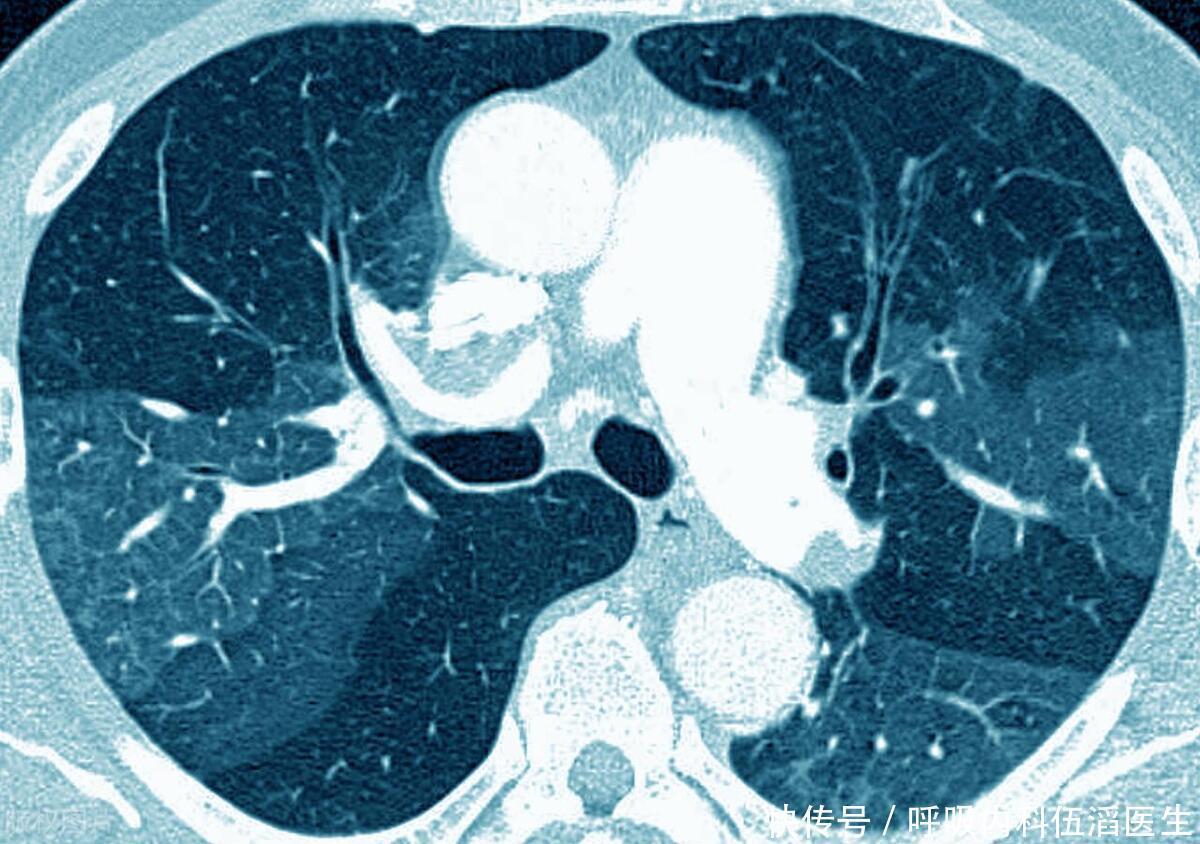

体内有“肺结节”的人,3 种“发物”要少碰,忍住不吃就很厉害了

肺结节

肺癌

肺腺癌